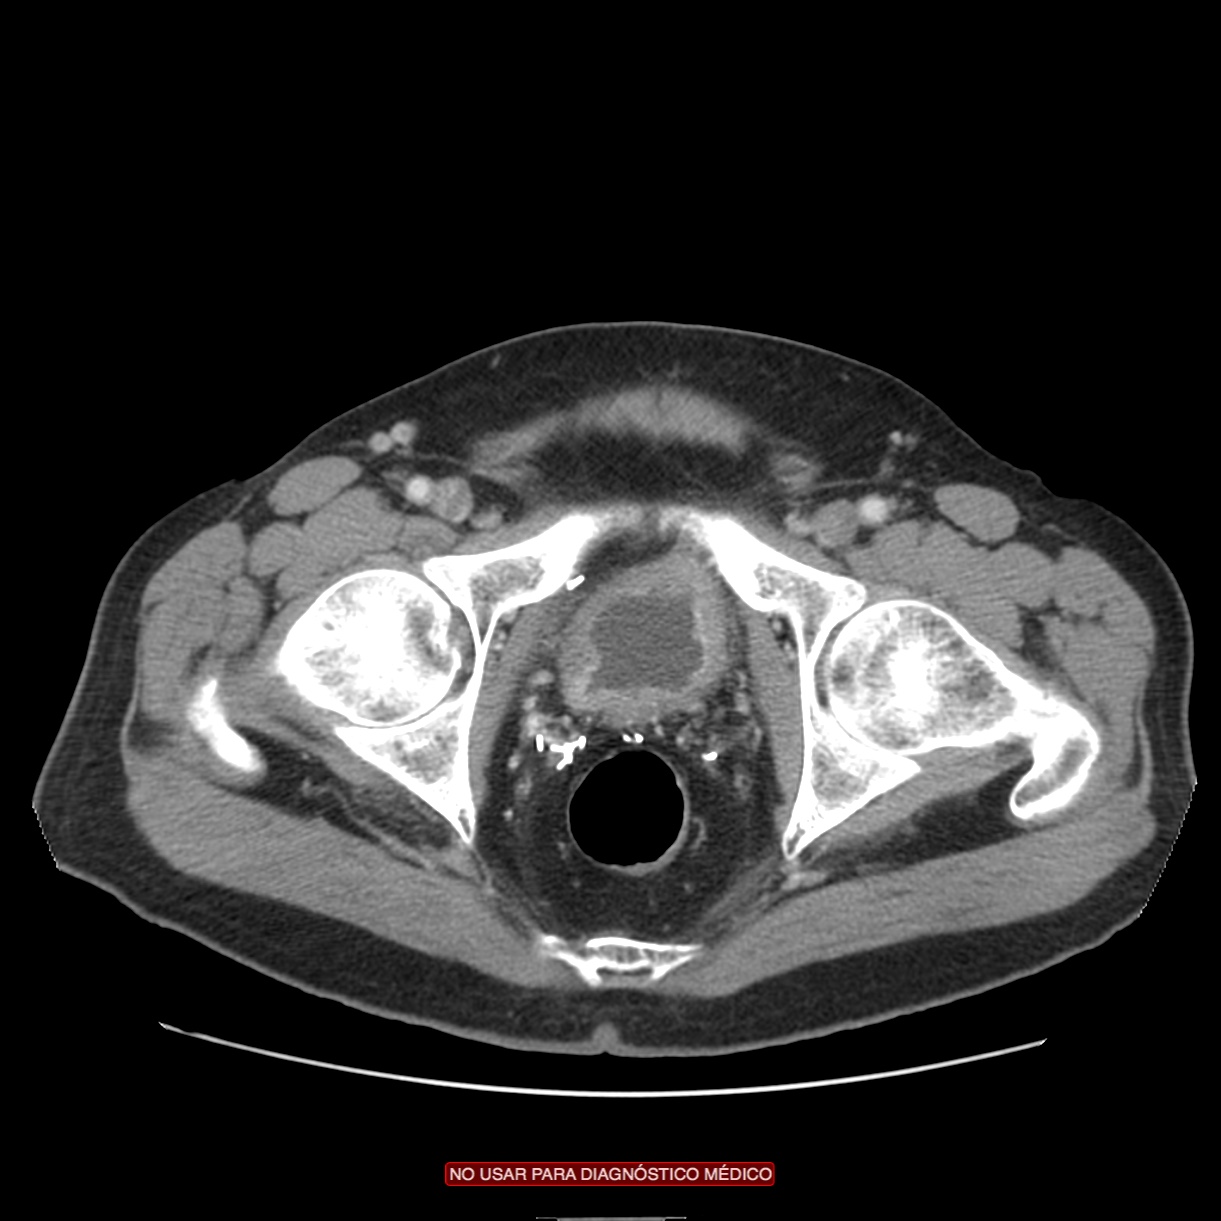

CASO CLÍNICO: Recopilatoción.

Paciente de 59 años con antecedentes personales de Cá de vejiga.

Se le realiza una Uro-Tc por seguimiento al año, aunque en esta ocasión el paciente refiere episodio de hematuria.

Tras el tratamiento de la recidiva y nefrostomía para la hidroureteronefrosis, vuelve acudir al hospital a los 9 meses por episodio de dolor en FD y malestar general. Se realiza una ecografía de urgencias.

Se realiza nueva TC bifásico abdominopélvio y Uro TC.

- Paciente con numerosas recidivas por Cá vejiga.

- Ha desarrollado un tumor metacrónico en pelvis renal derecha, también responsable de la hidroureteronefrosis.

- Mala evolución radiológica del proceso a expensas de metástasis pulmonares y hepáticas.